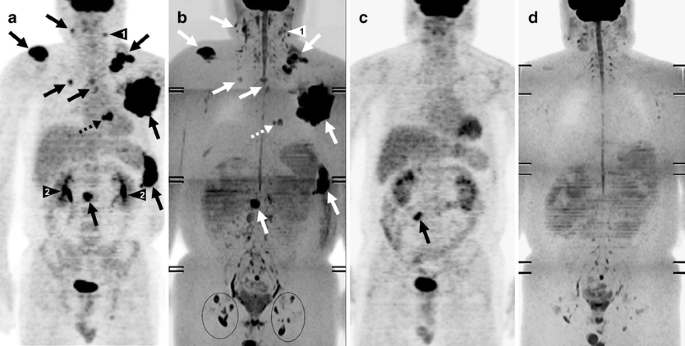

Fig. 10

Comparison of pre- and post-chemotherapy FDG-PET and DWIBS images in a 44-year-old man with diffuse large B-cell lymphoma. a Coronal maximum intensity projection FDG-PET and b coronal maximum intensity projection DWIBS images before initiation of chemotherapy. Both images show cervical, bilateral supra/infraclavicular, mediastinal, left axillary, para-aortic lymph node, and splenic involvement (arrows), and cardiac involvement (dashed arrow). c FDG-PET and d DWIBS images at the end of treatment show resolvement of all pre-existing lesions. a, b A limitation of DWIBS is that discrimination between normal and metastatic lymph nodes is still based on size criteria; the FDG-PET positive left cervical lymph node (arrowhead 1) cannot conclusively be identified as malignant on DWIBS (arrowhead 1). DWIBS also shows prominent bilateral inguinal lymph nodes (encircled) which are normal according to FDG-PET. On the other hand, thanks to its higher spatial resolution, DWIBS visualizes two separate cardiac lesions (dashed arrow), whereas FDG-PET shows only one large cardiac lesion (dashed arrow). DWIBS also allows better evaluation of the urinary tract than FDG-PET, where potential lesions can be obscured because of FDG accumulation (arrowheads 2). c Note the physiological FDG uptake in the large intestine (arrow), which should not be confused with persistent malignant lymphoma